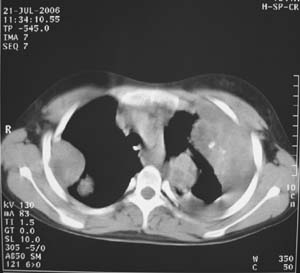

女性,17岁,一年前因股骨病变截肢,现胸憋。

左肺巨大肿块,内散在斑点状高密度骨化影,右肺见多发结节灶,双侧胸膜局限性增厚。有骨肉瘤病史,支持骨肉瘤手术后转移。